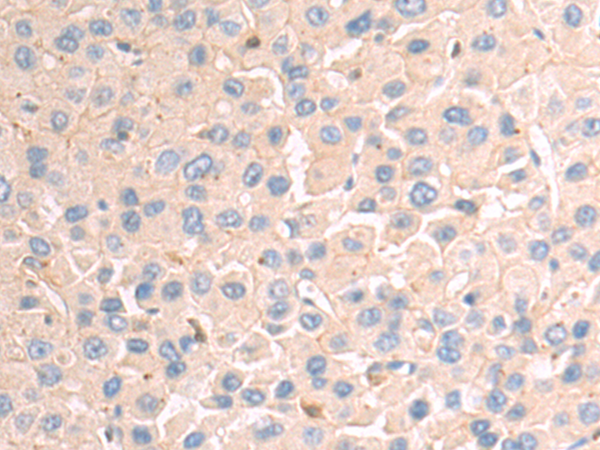

分类: 科研抗体货号: P04967别名: GPAPP; IMP 3; IMP-3; IMPA3应用: IHC反应种属: Human, Mouse, Rat